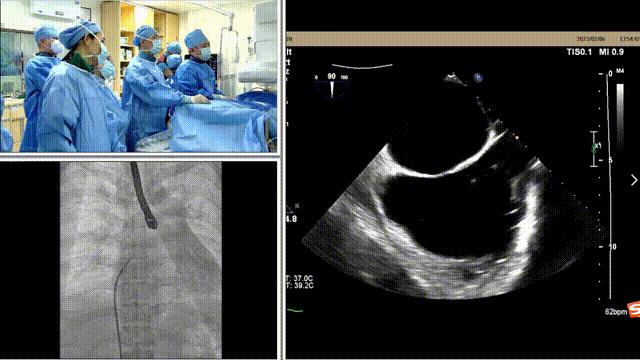

手术在全麻状态下进行,在食道超声和DSA引导下,经皮经股静脉建立路径、并穿刺房间隔,瓣膜夹通过输送系统送入左心房,顺利到达病变二尖瓣区域。

房间隔穿刺

导引鞘植入